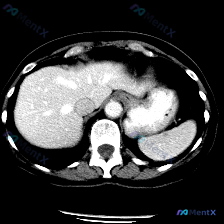

最近看到一个读片资料,预设问题是“图像中是否存在脾脏病变”,先和大家理一下完整的思路。 --- 先列一下拿到的「影像客观事实」 这是一幅上腹部CT软组织窗横断面图像: 1. 肝脏:轮廓平整,实质密度均匀,肝内血管走行清晰,无受压移位; 2. 脾脏:划重点——形态正常、大小正常、实质密度均匀,未见局灶...

今天看到一个很有意思的影像案例,用户一开始就预设了「脾脏病变」的存在,但当我仔细看完这张单层面的上腹部CT平扫后,发现结论可能和预设不太一样。整理一下思路和大家分享。 --- 先看影像基础信息 这是一张上腹部CT横断面软组织窗图像,层面清晰,软组织对比度良好,没有明显运动或金属伪影。能看到肝脏、胃、...